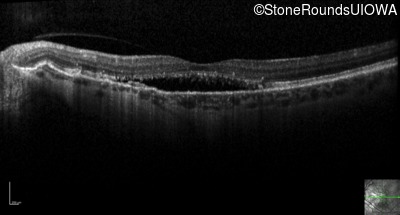

Optical Coherence Tomography - Right - 20/25 +2 sc

Exemplar / OCT Stack